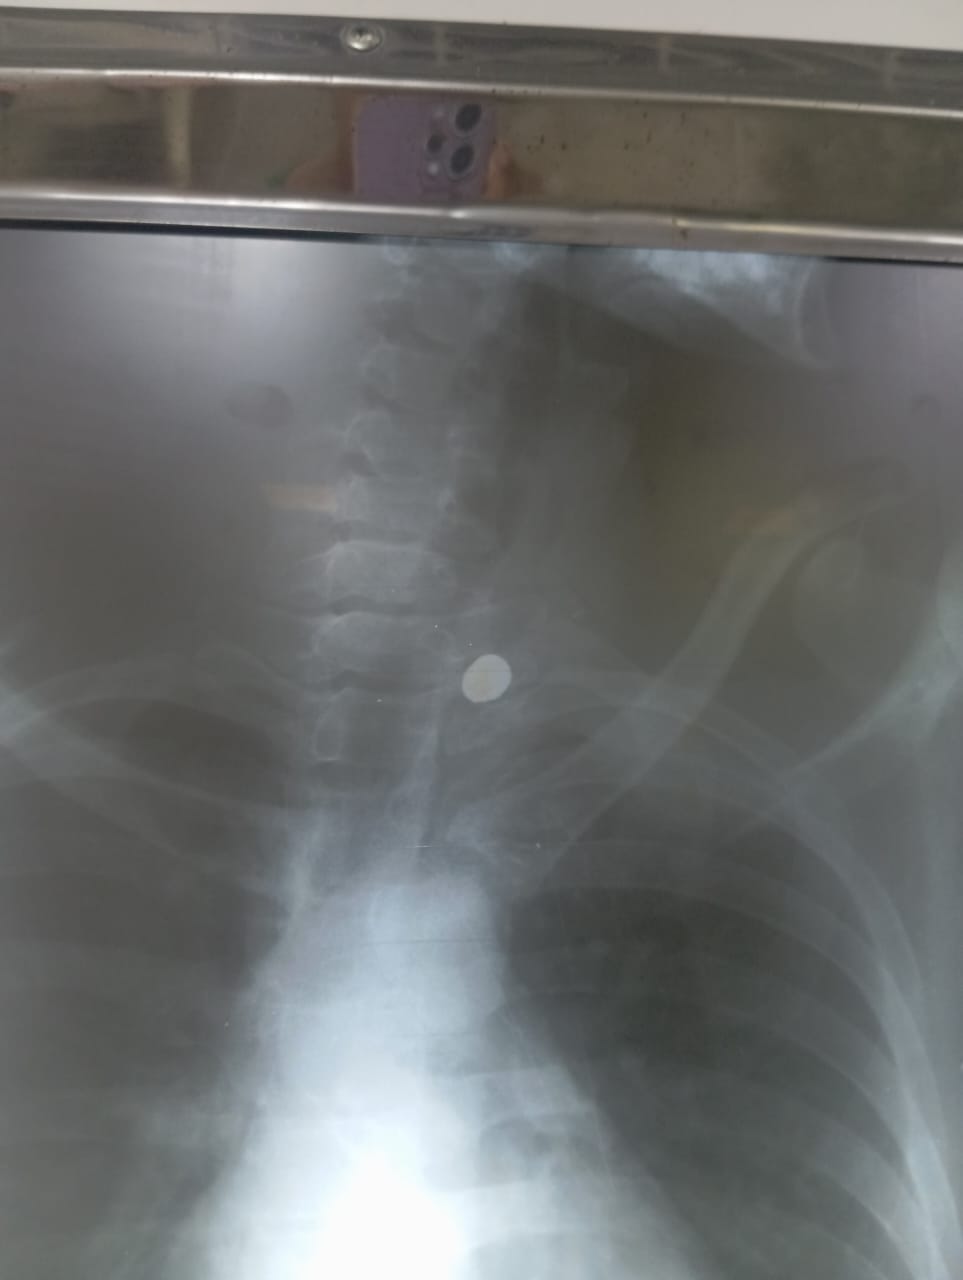

De acordo com informações médicas obtidas pela reportagem junto a fontes ouvidas sob condição de anonimato, a bala percorreu uma área considerada de alto risco. A equipe médica optou por não realizar a cirurgia de retirada, diante da possibilidade de o procedimento causar sequelas graves, como tetraplegia.

Além disso, o jovem sofreu fratura em algumas vértebras, e o projétil ficou alojado próximo à parede do pulmão.